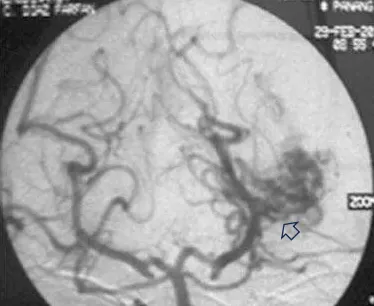

首次手术仅仅三个月后,令大卫一家担忧的事情还是来临了。大卫在学校突然昏迷,紧急送往医院后,检查为左侧颞角的AVM导致脑室内出血(图ab)。Spetzler-Martin分级4级:S1V1E1/A1B0C0,供血来自AChA(脉络膜前动脉)。

图(b)左侧VA造影,前后位像